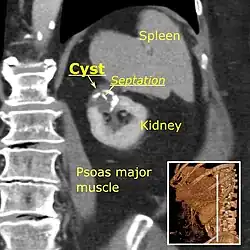

-

Renal ultrasonography of a simple renal cyst with posterior enhancement. -

Advanced polycystic kidney disease with multiple cysts.[13] -

Renal cyst as seen on abdominal ultrasound -

A very small (8 mm) simple renal cyst. -

Bosniak II cyst at the lower pole of right kidney with septations within.